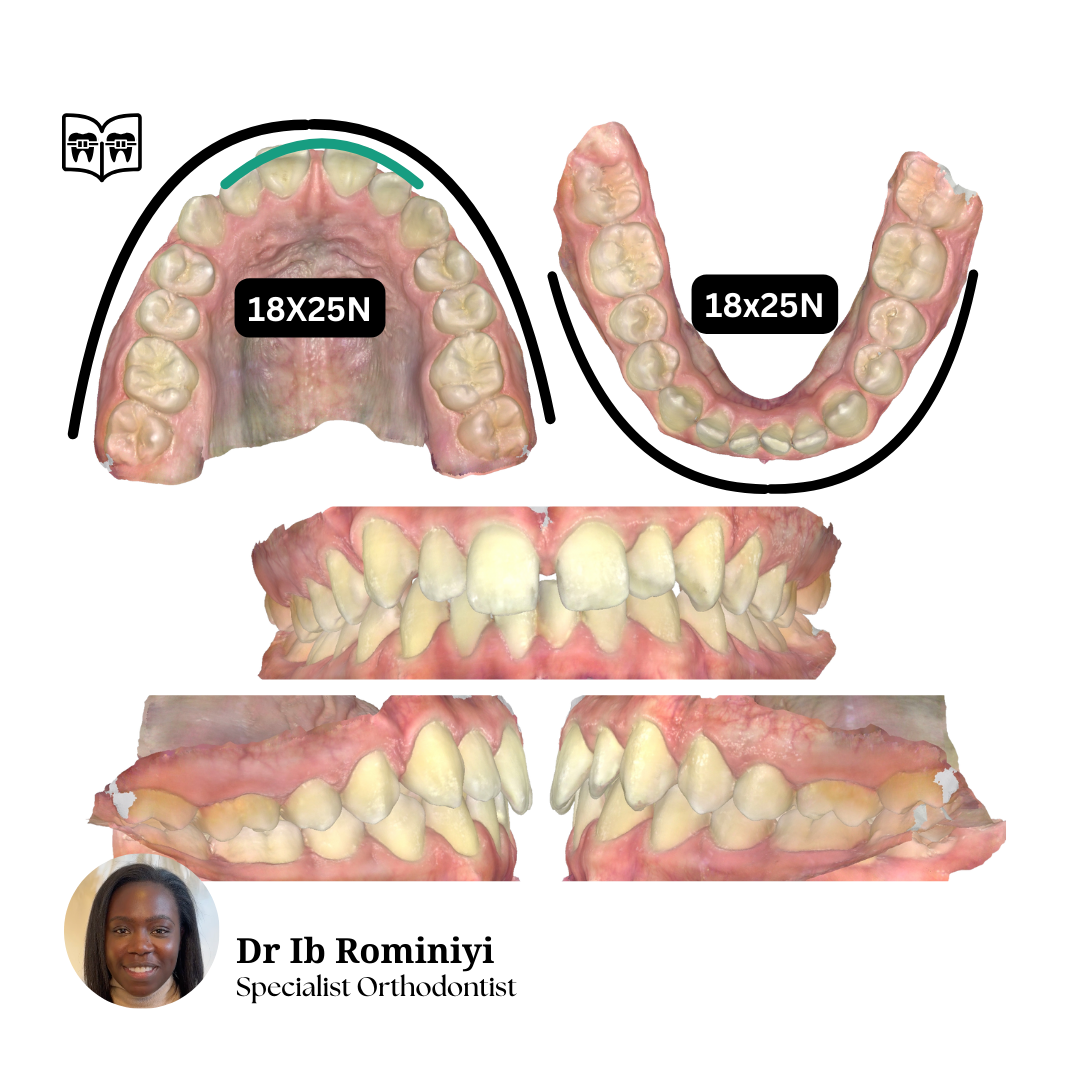

M E N T O R I N G M O M E N T

#1

Dentist's Question: I'm currently in upper 19x25N, lower 18x25S and the lateral open bites and centrelines are getting worse.

How would you improve the bite?

What mechanics & archwires would you use from here?